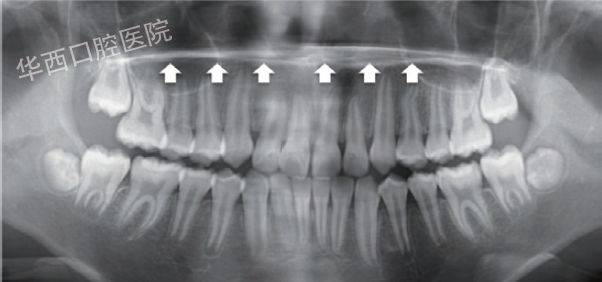

曲面体层片正常结构

曲面体层片正常结构,人体结构

口腔曲面体层片中的奥秘—唐蓓博士

曲面体层片显示:18,28,38,48存在.

口腔曲面体层片中的奥秘—唐蓓博士_结构